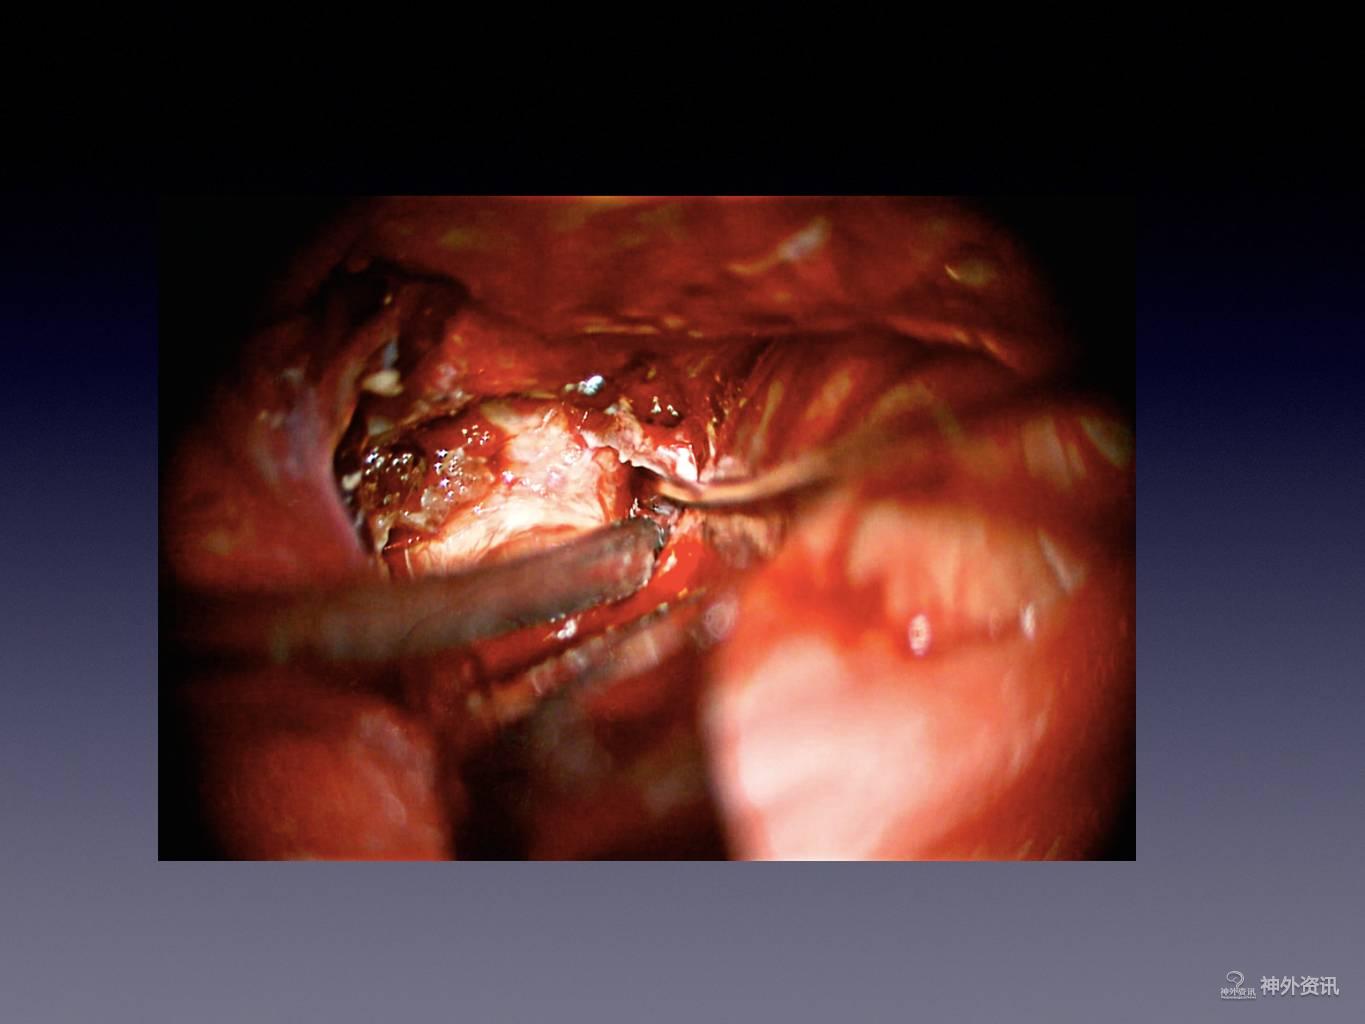

王林教授:床突旁动脉瘤夹闭手术

今天为大家分享的是《正海-妙术视界》第二十二期,由浙江大学医学院附属第二医院神经外科王林教授带来的床突旁动脉瘤夹闭手术,视频非常精彩,欢迎观看。